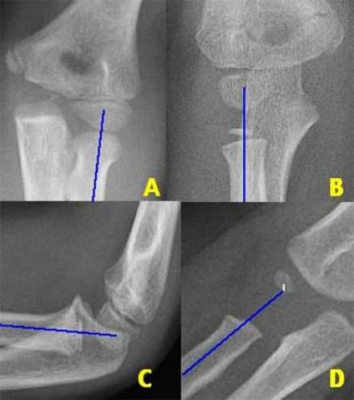

Gãy trên lồi cầu xương cánh tay ở trẻ em

- Đây là loại gãy xương ở khuỷu tay phổ biến nhất ở trẻ em. Hầu hết những gãy xương này tạo ra sự dịch chuyển ra sau của đầu dưới xương cánh tay.

- Trên phim nghiêng, đường trước xương cánh tay (đường tiếp tuyến với vỏ xương cánh tay phía trước) bình thường sẽ chia đôi phần ba giữa của chỏm con (capitellum) xương cánh tay. Trong gãy trên lồi cầu cầu, đường này đi ra trước vị trí bình thường của nó (Hình 18).